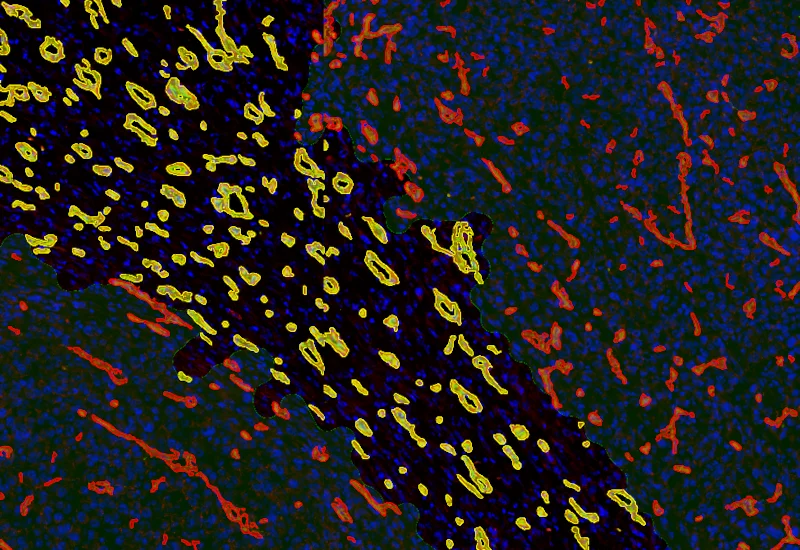

Original Image

Vessel detection

Combined detection